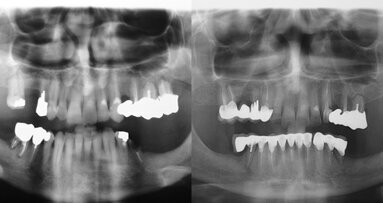

Il paziente G.P. di anni 58, professione impiegato tecnico, si rivolse nell'ottobre 2005 a un Centro Medico Odontoiatrico di Torino per riabilitare ...